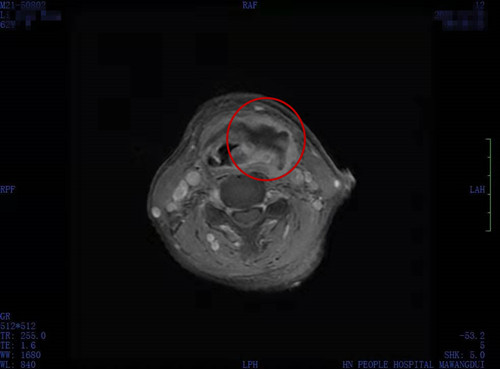

接诊的王宁主任通过电子喉镜发现,李阿姨的会厌、梨状窝明显红肿充血,声门变形,结合李阿姨多年糖尿病的情况,王宁主任告诉李阿姨,她的情况比较危重,并不是普通的感冒那么简单,需要住院治疗。李阿姨入院后还直犯嘀咕,就一个喉咙痛,怎么还需要住院治疗?当医生把病情解释给她听,李阿姨才明白,自己喉咙痛的原因可能是坏死性颈筋膜炎,咽喉及咽旁都有脓肿形成,若不及时治疗,随时有生命危险。

王宁主任团队立即为李阿姨安排了手术,术中彻底清除坏死组织,引流脓液。术后经过精心的治疗和护理,李阿姨在年前顺利出院。